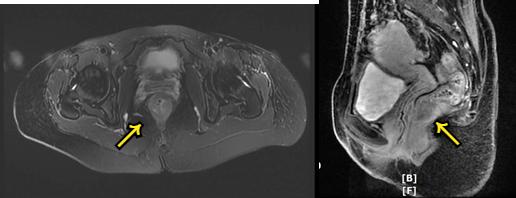

术前MRI(2019.6)

术后复发MRI(2021.1):骶前区肿瘤复发并累及阴道